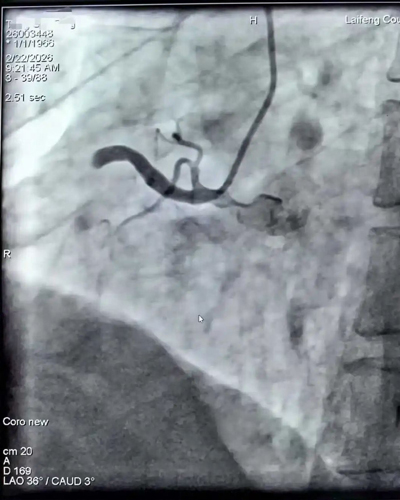

心血管内科:全天候诊,守护“心”的跳动

春节期间,情绪波动、劳累、饮食油腻等因素,使得心血管疾病如同隐匿的“杀手”随时可能发作。在心内科,这里的春节没有觥筹交错,只有仪器的滴答声。

医护人员严阵以待,急性心梗绿色通道24小时畅通。为了应对可能出现的急危重症,他们放弃了休假,时刻紧盯监护仪上跳动的曲线。每一次成功的抢救,每一次让濒临停摆的心脏恢复有力的搏动,都是他们对这个春节最深情的告白。

春节期间开通血管后植入支架